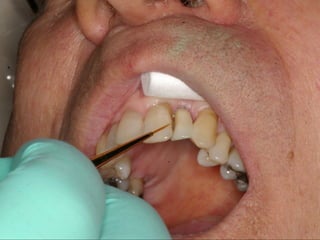

This document discusses several dental implant cases where porcelain crowns were used to restore teeth. It describes the process for each case, including placing implants, attaching provisional crowns, modifying the crowns, adding porcelain, and delivering the final restoration. Photos show before and after images for each case, which include replacing premolar teeth, bridges, and full upper dental arches.